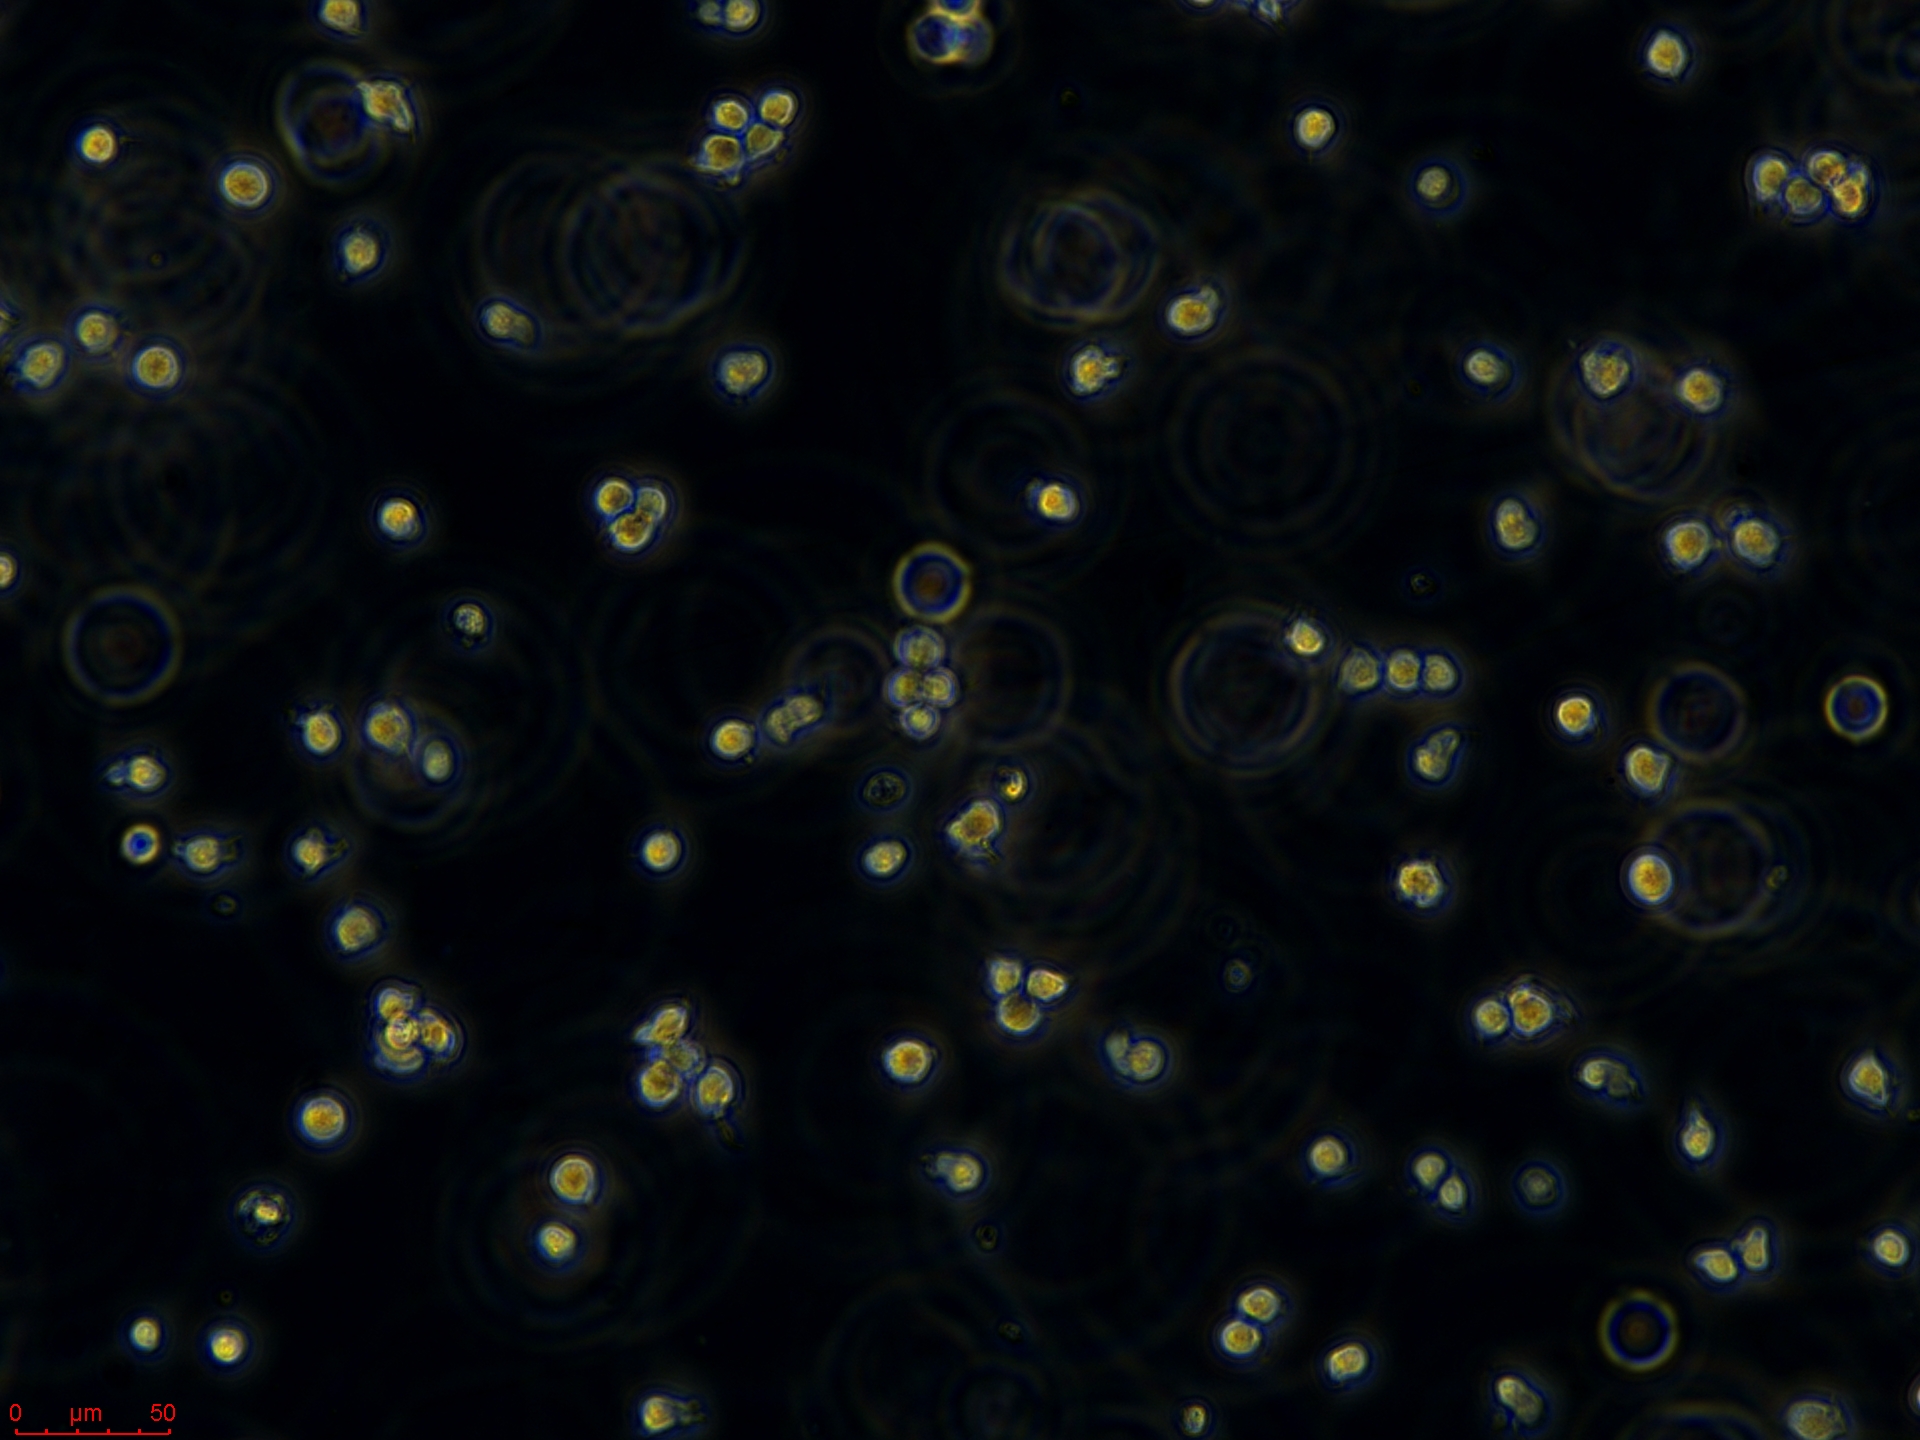

Jurkat细胞(人外周血白血病T细胞),是一种悬浮细胞。我的经验如下:1、培养液:RPMI1640,15%小牛血清,2%Na2CO3,1%HEPES,青霉素100IU/1ml,庆大霉素100IU/ml;2、培养条件:5%CO2,37度,30%湿度;3、细胞复苏:要快速将冻存管放入37度水中,不断轻轻摇晃,直到细胞完全溶解,加入10ml左右的培养液,800~1000rpm,10分钟离心,之后倒掉液体,加入新的培养基就可以进行培养了;4、细胞培养:起初进行传代时由于细胞刚刚复苏,长得比较